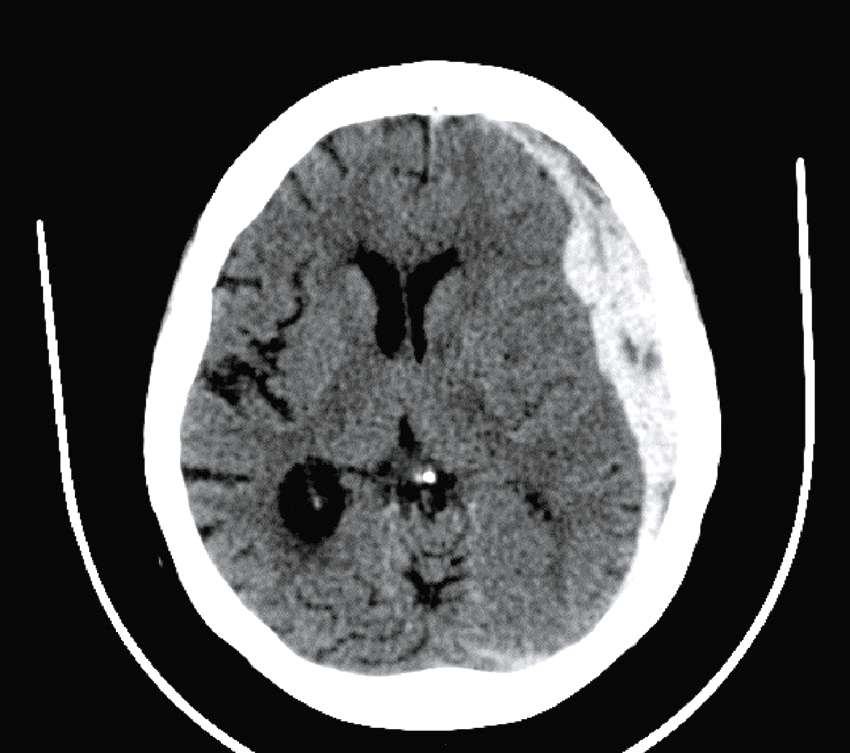

Question 4 – QRMVoici une coupe axiale d’un scanner cérébral sans injection (fig. 31.9). Concernant son interprétation, quelle(s) est (sont) la (les) proposition(s) exacte(s) ?

Fig. 31.9 L'image montre une coupe transversale d'un scanner cérébral (CT scan) d'un cerveau humain. Cette image en noir et blanc présente des détails anatomiques du cerveau, y compris les structures internes et les contours du crâne. Les zones claires représentent les tissus osseux, tandis que les zones sombres indiquent les tissus mous du cerveau. On peut observer des variations dans les nuances de gris qui révèlent différentes densités de tissus. Les ventricules cérébraux, qui sont des cavités remplies de liquide céphalo-rachidien, sont également visibles au centre de l'image. Ces cavités apparaissent sombres en contraste avec les tissus environnants. La partie périphérique de l'image montre les os du crâne, apparaissant comme des lignes blanches bien définies. Les scanners cérébraux sont des outils essentiels pour diagnostiquer et surveiller diverses conditions neurologiques. Ils permettent de détecter des anomalies telles que des hémorragies, des tumeurs ou des lésions cérébrales. Les variations de teintes visibles sur l'image aident à différencier les structures et à évaluer leur état, fournissant ainsi des informations cruciales pour les professionnels de la santé. Grâce à ces images détaillées, il est possible de planifier des traitements adaptés et de surveiller l'évolution des pathologies cérébrales.

- A hyperdensité spontanée des vallées sylviennes

- B hyperdensité spontanée du sinus maxillaire droit

- C hypodensité spontanée de l’épiphyse

- D hyperdensité spontanée du 4e ventricule

-

E hypodensité spontanée des plexus choroïdes